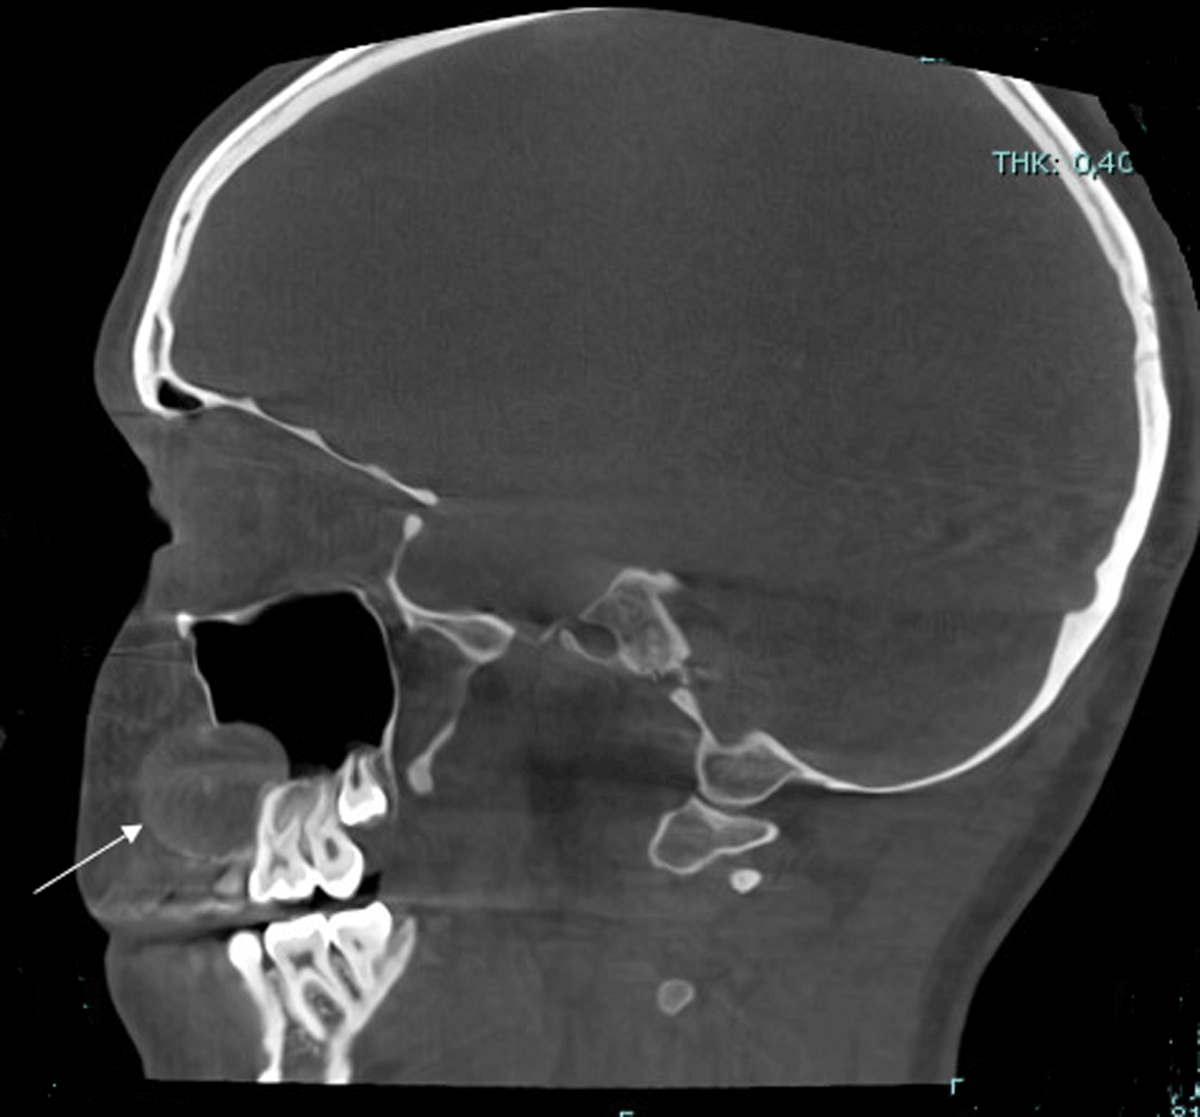

The lesion had an expansive character with loss of cortical delineation of the anterior wall of the right maxillary sinus (Figure 3).

Figure 3